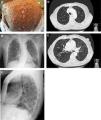

A 62-year-old woman with a past smoking history of 100packs/year without preceding pulmonary pathology but previously diagnosed with NF1 (sporadic form) in her youth. She had been diagnosed a year earlier of an infiltrating ductal carcinoma in her right breast treated with sequential neoadjuvant therapy and subsequent mastectomy. She was treated in Emergency Department because of fever and cough in the previous 4 days. Physical examination showed bilateral wheezing without other relevant findings, except for countless neurofibromas (Fig. 1A). Leukocytosis with left shift and acute respiratory failure was observed. Chest radiograph displayed thickening of peribroncovascular interstice with left basal predominance (Fig. 1B, C) and multiple and bilateral irregular thin-walled aerial cysts were seen in the high resolution computed tomography (CT), converging in upper zones mimicking emphysema (Fig. 1D, E). Her pulmonary function tests were: FVC 1400cc (61.7%); FEV1 890cc (47%); FEV1/FVC 63.4 (77.3); DLCOsb 29.2%; DLCO/VA 39.3%. Based on these findings, diagnosis of NF1-DLD was established (without any other organs involved). Following oxygen, bronchodilators, antibiotics (levofloxacin) and corticosteroids treatment, she presented a favorable outcome and was discharged from hospital after 4 days.

(A) Multiple cutaneous neurofibromas in a NF1 patient. (B, C) Chest X-ray in which thickening of the peribroncovascular interstice with left basal predominance is observed. (D, E) High resolution computed tomography (axial plane and pulmonary window) through upper lobes above and below carina showing multiple thin-walled irregular aerial cysts, that tend to converge in upper areas, with similar appearance to emphysema.